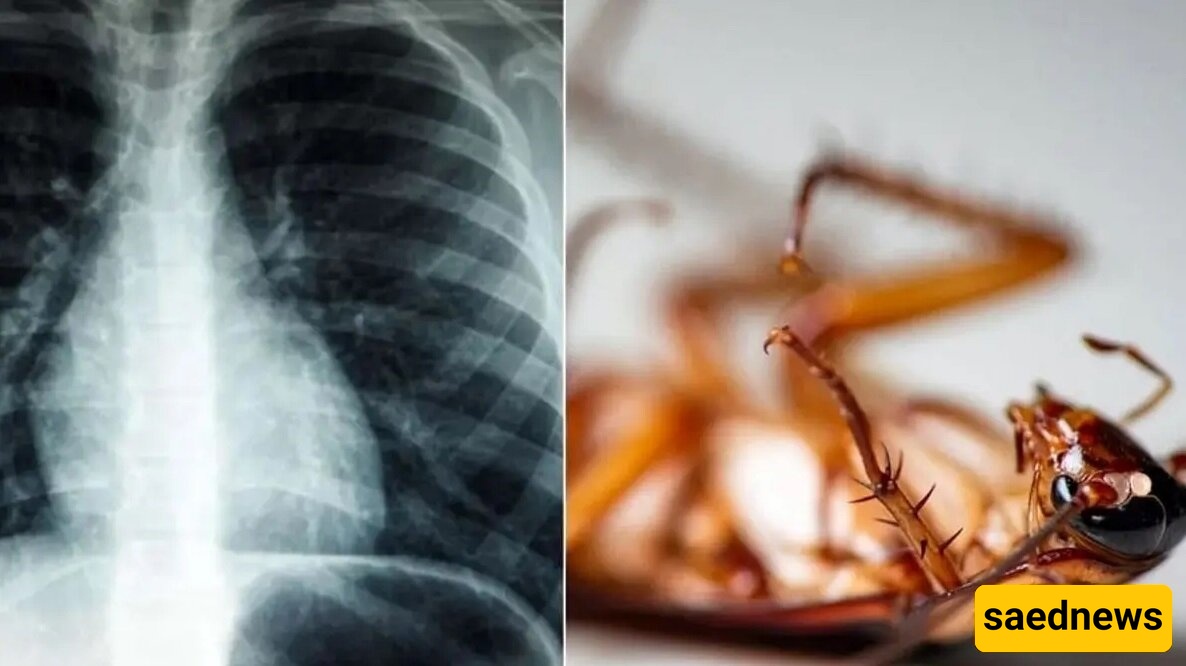

إزاله صرصور حی بطول 4 سنتیمترات من رئه رجل یبلغ من العمر 55 عامًا

وفقًا لتقریر الشؤون الاجتماعیه لوکاله ساعدنیوز، نقلاً عن صحیفه همشهری، زار رجل یبلغ من العمر 55 عامًا مستشفى فی ولایه کیرالا الهندیه، مُبلغًا عن شعوره بتوعک صحی. أدت مشاکل فی الجهاز التنفسی إلى قیام الأطباء بإجراء تنظیر للشعب الهوائیه، حیث اکتشفوا وجود صرصور یبلغ طوله أربعه سنتیمترات داخل رئته.

یقترح الأطباء أن الحشره دخلت على الأرجح رئته عبر أنبوب سبق أن تم إدخاله فی حلقه لتوصیل الأکسجین.